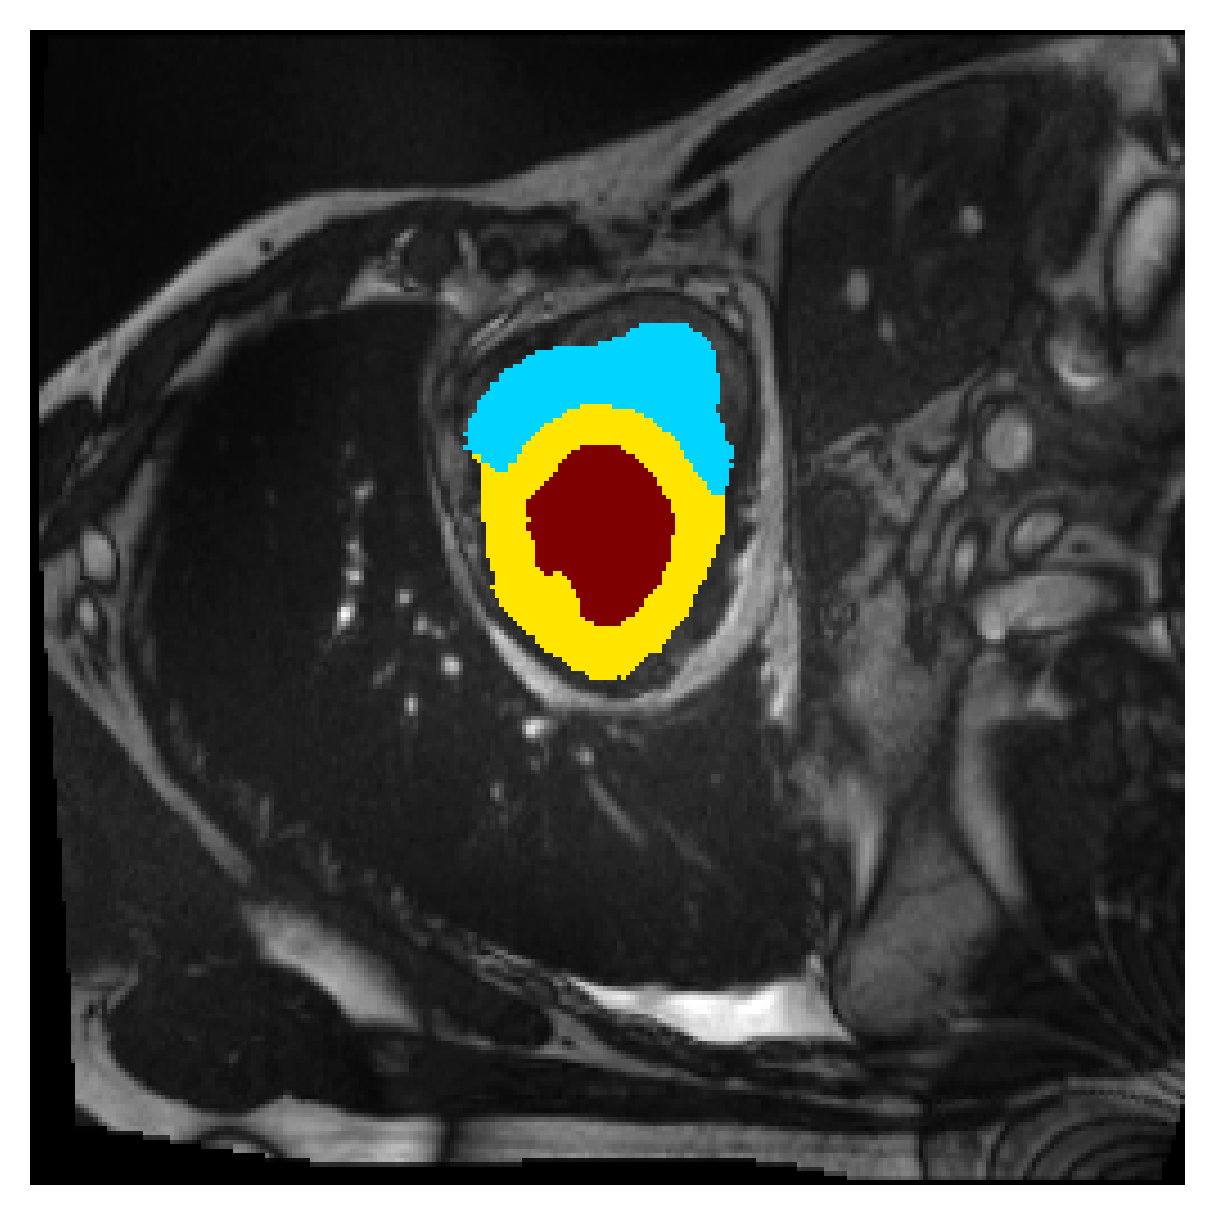

Qualitative comparison

| (a) Ground truth | (b) , full | (c) , weak | (d) |

| (full) | supervision | supervision | |

|

|

|

|

|

|

|

|

|

|

|

|

| (e) | (f) | (g) | (h) CRF-loss |

In Figure 6 we provide qualitative results on a number of randomly chosen test set slices. Upon visual inspection, we can observe that training with the intensity-aware distances (particularly with and ) follows the image gradients better and is better at recovering the underlying shape than the Euclidean version. The CRF-loss seems to recover the shape of the myocardium and left ventricle to some extent, but fails entirely on the right ventricle.